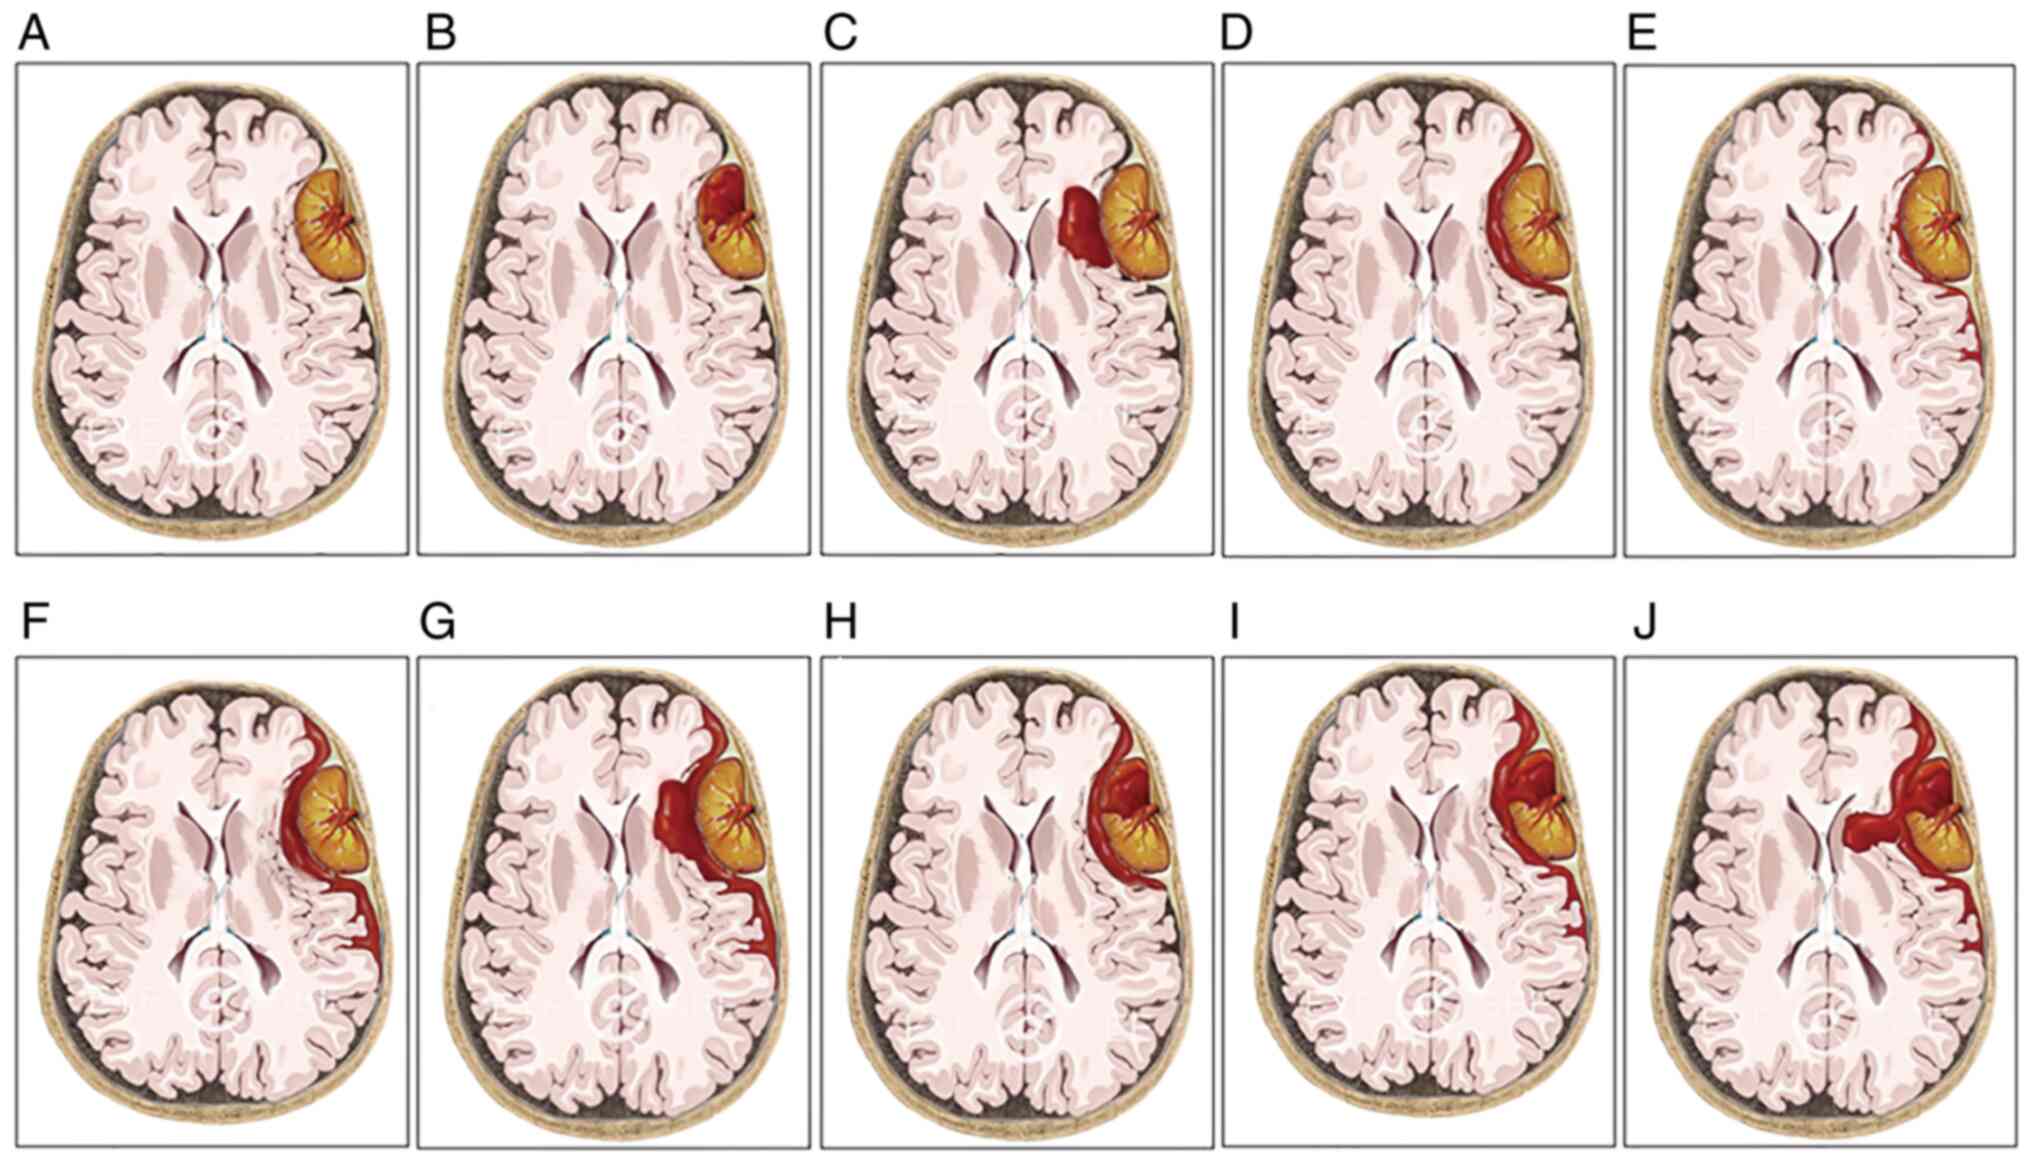

Meningiomas are the most common benign intracranial tumors and frequently present with a gradual onset of neurological deficits; conversely, their acute presentation with hemorrhagic onset appears to be a rare event. Nonetheless, as early surgical evacuation is the foundation of treatment, a timely diagnosis of this rare type of intracranial hemorrhage is necessary. The purpose of the present single‑center study was to investigate the radiological characteristics and propose a new bleeding classification for guiding the diagnosis and treatment. A total of 19 patients consecutively diagnosed with hemorrhagic meningioma were enrolled in this retrospective study. Intracranial extra‑axial mass, tumor‑associated hemorrhage and peritumoral brain edema were the three main radiological features of the hemorrhagic meningiomas. The site of tumor‑associated hemorrhage included the peritumoral space, subarachnoid space, subdural space, brain parenchyma and/or intratumor region. Based on the anatomical relationship between meningioma and hematoma, the spontaneous hemorrhage stemming from meningiomas was further summarized into three bleeding patterns involving purely intratumoral hemorrhage (type I), purely extratumoral hemorrhage (type II) and combined intra/extratumoral hemorrhage (type III); furthermore, the type III hemorrhage usually came from type I bleeding that extended into the surrounding regions. The symptoms in type I patients were generally mild and early surgery was performed following adequate preoperative evaluations. The symptoms in type II patients were mild in certain cases and moderate to severe in others, so early or emergency surgery was chosen according to the clinical status of the patient. Almost all type III patients had moderate to severe symptoms and these patients usually required emergency surgery. In addition, patients with different bleeding types may have different pathological mechanisms underlying the tumor bleeding. Apart from being convenient for diagnosis, this concise and practical bleeding classification may aid in the selection of the treatment strategy and facilitate the understanding of the associated mechanisms.

Figure 1

Figure 2

Figure 3

Figure 4

Figure 5

Figure 6

Figure 7

Figure 8

Figure 9